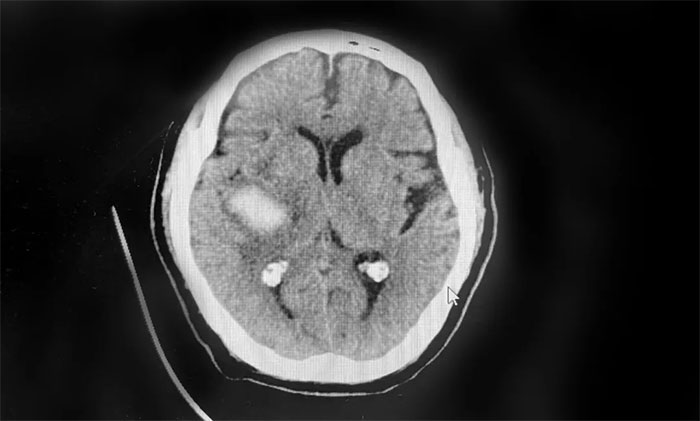

优质服务 ︱ 抓住脑出血后“黄金康复期” 精心救治助患者恢复行走能力

脑出血往往起病突然、急性发作,即使在全力抢救后仍有较高的致残、致死率,严重威胁着患者生命健康。规范的早期康复治疗,则是提高患者生活质量、防止疾病复发的重要手段,越早介入,获益越大。...【详细】